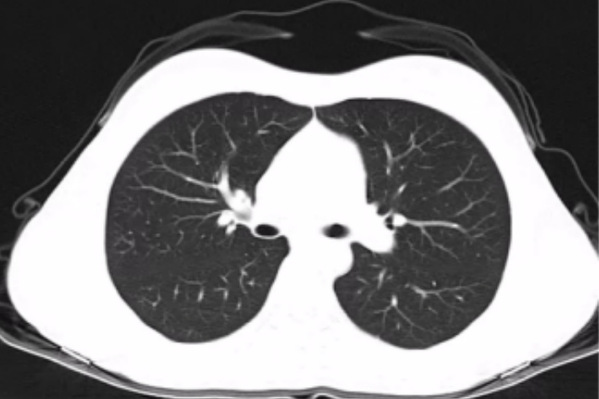

肺结节为小的局灶性、类圆形、影像学表现密度增高的阴影(直径≤3cm),可单发或多发。肺结节通常分为三种类型:

(1)纯磨玻璃结节:指在薄层CT上病变边界清楚的类圆形肺内密度增高影,但病变密度不足以掩盖其中的细小血管和细支气管影。

(2)混杂磨玻璃结节:指纯磨玻璃结节内出现明显实性成分。

(3)实性结节:指主要明显实性成分的结节。

我们来更直观的感受下这三种结节的差异,如果说纯磨玻璃结节是个大馒头,那么实性结节就像是个完完全全的豆沙馅,混杂磨玻璃结节就像是个豆沙包。

在恶性概率上:混杂磨玻璃结节 > 纯磨玻璃结节 > 实性结节